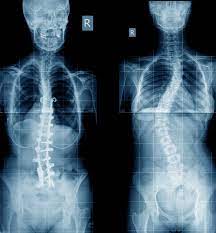

KYPHOSIS SCOLIOSIS CORRECTION SURGERY

Spine surgery for kyphosis is recommended for patients whose curvatures continue to progress or cause symptoms despite non-operative treatment. Corrective surgery for thoracic kyphosis is usually recommended when curves are larger than 80° to 90° when measured on x-rays. Kyphosis can extend into the mid or lower back and in those cases surgery is recommended for curves larger than 60° to 70° of kyphosis. Surgery is also an option for patients with disabling back pain or when kyphosis leads to compression of the spinal cord or nerves.

The goal of spinal reconstruction surgery is to decrease the patient's pain and to place the spine in a more natural position. Most commonly this surgery is performed through a posterior approach in the back of the spine. During the surgery, spinal implants including rods and screws are placed next to the spine. These implants correct the spinal deformity and stabilize the spine in its new position while the spine fuses, or mends, together. These bones ultimately heal into one solid piece for spinal stability and prevention of further curve progression. Complications may occur but are not common.

The majority of patients are satisfied with their pain relief and the results of their surgery. It is important that all patients are physically and psychologically prepared. All patients should stop smoking prior to any surgery, as smoking is extremely detrimental to your spine health, potential bone healing and successful surgical outcomes. Please review additional details with your surgeon prior to your surgery.